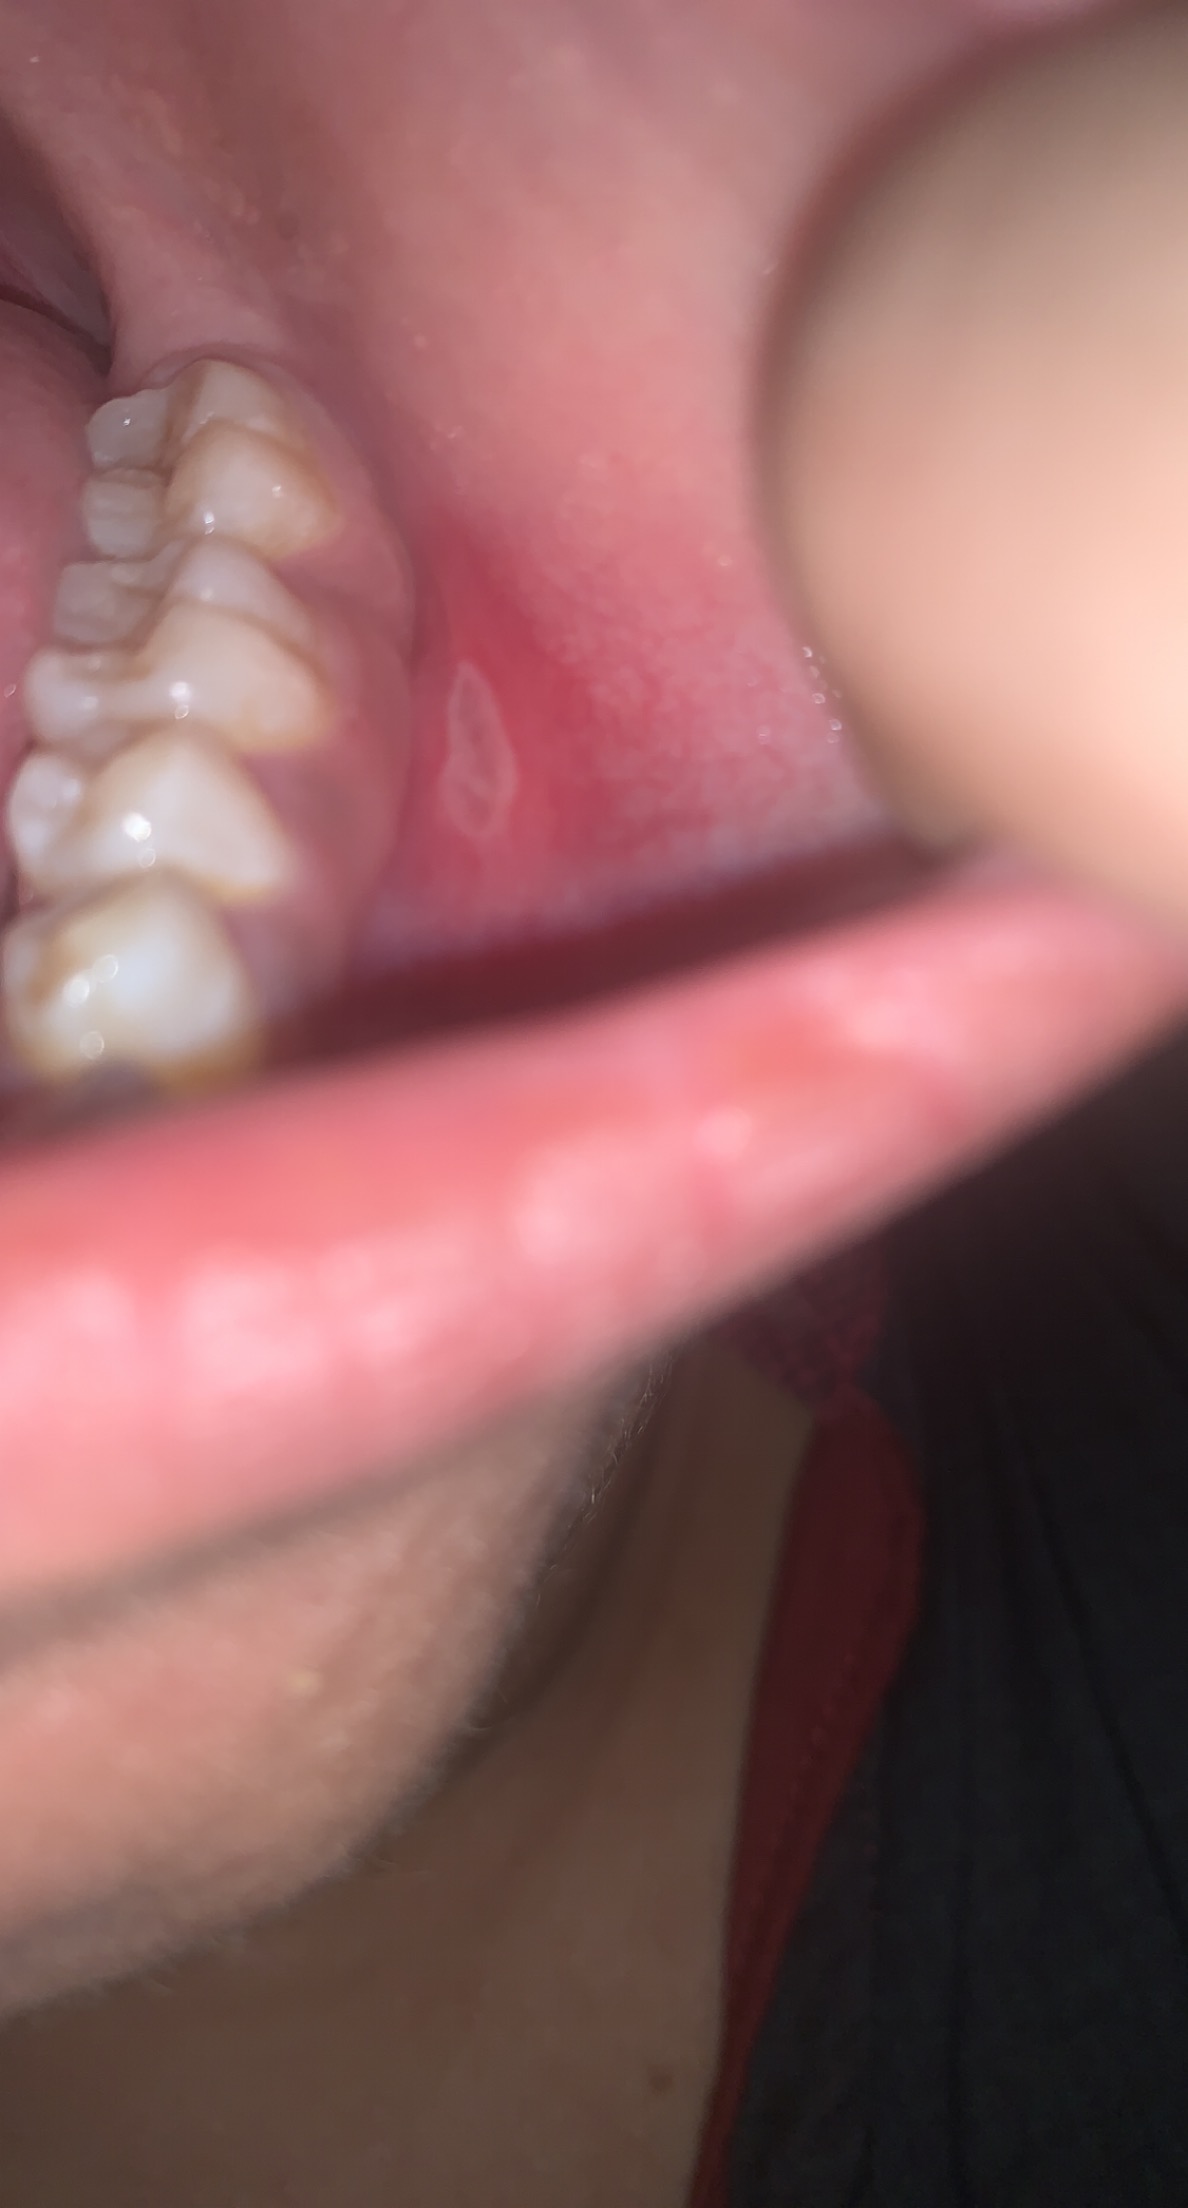

Asking for Self, Female, 27 years old, Karchi

I am having mouth sore, umm which small and have gotten little big and whenever i google it just talk about cancer, really worried and anxious

normal ulcers do not last longer than 4 weeks, please see your nearest dentist for proper diagnosis for the time being use removit plus gel over the ulcer for relief.

Duration of ulcer plz??? If not more than 2 to 4 weeks than no worries & do consult your nearest dental surgeon for timely diagnosis and treatment.Thankyou

Consult a dentist for better diagnosis ... you don't know the actual reason of these ulcers .till then use a mouthwash for better oral hygiene and a gel preferably Revomet plus. apply gel on ulcers and leave it for alteast 4 to 5 hours. it will gives you better results. but in the end you need to consult a dentist for its proper diagnosis.

Low Level Laser Therapy will be much helpful in treating these type of ulcers.